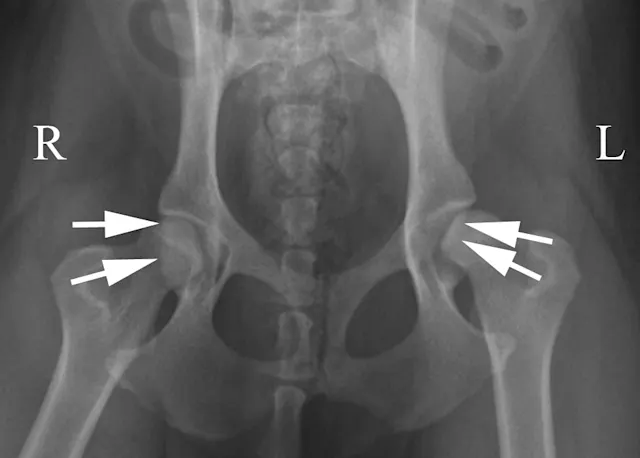

If the stifles are kept internally rotated, the patella should be centrally located over the distal femurs, as seen in the normally positioned radiograph (Figure 1B). In this image the femurs are parallel with each other and parallel with the imaging plate. Note the uniform and equal size of the obturator foramen on this well-positioned radiograph. Ideally, the sacrum, ilial wings, and entire 7th lumbar vertebra should be included in the image. Figure 1C shows an example of the pelvis correctly positioned.

Pelvic radiographs must be assessed for adequate positioning and should be repeated if the pelvis is oblique, as in Figure 2A. In this example, there are multiple positioning errors. The right femur/stifle should be further internally rotated (so the patella is more centrally located over the femur). The right stifle should be moved axially (medially) so the femurs are parallel. The pelvis is rotated with the right hemipelvis farther away from the imaging plate. In Figure 2B, the right hemipelvis has been elevated from the imaging plate. In this image, the right (up) obturator foramen is increased in width compared with the left. Additionally, the left (down) ilium appears narrower.

Oblique positioning will result in false assessment of dorsal acetabular rim coverage of the femoral head, as shown in Figure 2C. The dorsal acetabular rim (white arrows) appears to provide more coverage of the right femoral head and less coverage on the left side. When the patient is properly positioned, as in Figure 2D, it is evident that coverage of the dorsal acetabular rim (white arrows) is similar on both sides.